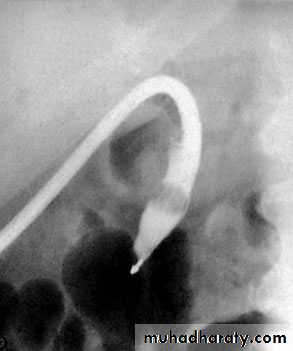

NORMAL ERCP

almadena copy